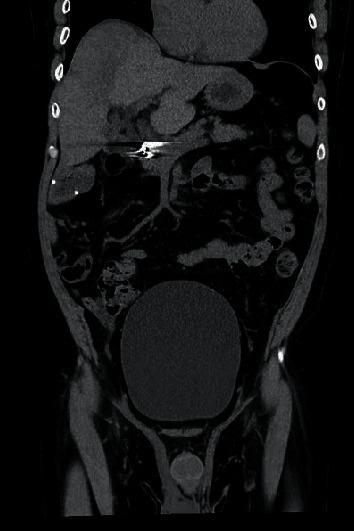

Antipsychotics are considered the most efficacious drugs in the treatment of schizophrenia and other psychotic disorders. While clinicians monitor for the onset of extrapyramidal symptoms (EPSs), many do not consider the antimuscarinic and histaminergic side effects that can occur with second generation antipsychotics. We present the case of a 62-year-old male who presented with acute urinary retention that was found to be due to the recent initiation of olanzapine. Gradual cessation of the medication and follow-up with urology revealed resolution of his symptoms. With the increasing demand for psychiatric care but limited psychiatric resources, more and more primary care physicians find themselves dealing with the complex challenges of mental illness and managing antipsychotic medications. As a result, coordinating care among multiple specialties and understanding the full profile of side effects that are associated with psychiatric medications can yield quicker diagnoses and improve patient care.

抗精神病药物被认为是治疗精神分裂症和其他精神障碍最有效的药物。虽然临床医生会监测锥体外系症状(EPS)的出现,但许多人并未考虑到第二代抗精神病药物可能出现的抗胆碱能和组胺能副作用。我们报告一例62岁男性病例,该患者出现急性尿潴留,发现是由于最近开始服用奥氮平所致。逐渐停用该药物并接受泌尿外科随访后,其症状得到缓解。随着对精神科护理需求的增加,但精神科资源有限,越来越多的初级保健医生发现自己在应对精神疾病的复杂挑战以及管理抗精神病药物。因此,协调多个专科之间的护理并了解与精神科药物相关的全部副作用情况,可以更快地做出诊断并改善患者护理。